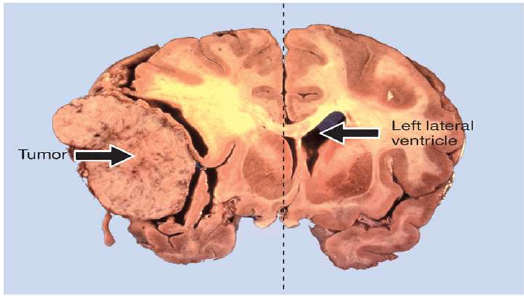

Glioblastoma Multiforme

Grade 4 Astrocytoma

• Most aggressive tumor form (grows in 1-2 months)

• Average survival rate from diagnosis approx. 2 years

• Higher Incidence in white individuals